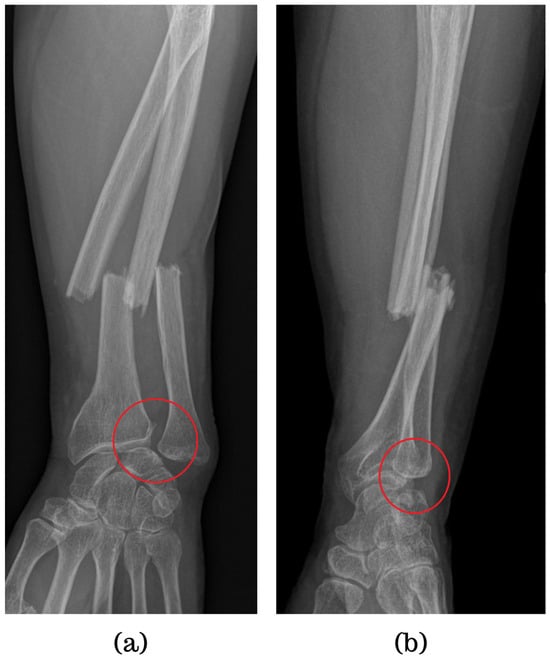

6.7. Galeazzi Fractures

Galeazzi fractures involve a fracture of the radius and dislocation of DRUJ [7,61], comprising about 7% of forearm fractures and often resulting from high-energy trauma [11]. Symptoms include forearm swelling and deformity [62]. Various classification systems categorize these fractures based on their location relative to the DRUJ and radial styloid involvement [63,64,65]. In adults, radial shaft fractures with distal ulna fractures are termed Galeazzi equivalents [62].

Accurate diagnosis relies on X-rays or CT scans to evaluate the DRUJ and detect neurovascular damage, although radiographic predictors of instability may not always be reliable (Figure 6) [7,62].

Figure 6. AP and lateral views of a Galeazzi fracture.